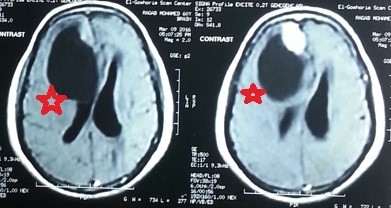

ورم سحائي بالفص الامامي الايمن بالمخ

meningioma in the right frontal lobe of the brain

A transverse view of an MRI scan of a 63-year-old patient suffering from epileptic seizures and weakness on the left side of the body showing a cystic meningioma in the right frontal lobe of the brain shaded in red. And the rays after excision with a microscopic surgery, where he completely disappeared, shaded in green. The pictures during surgery also show the solid part that was completely removed and the location of the tumor in the brain, as the brain after removing the hard part and emptying the cyst around it is completely intact. The patient has fully recovered after the surgery and is living his life normally.